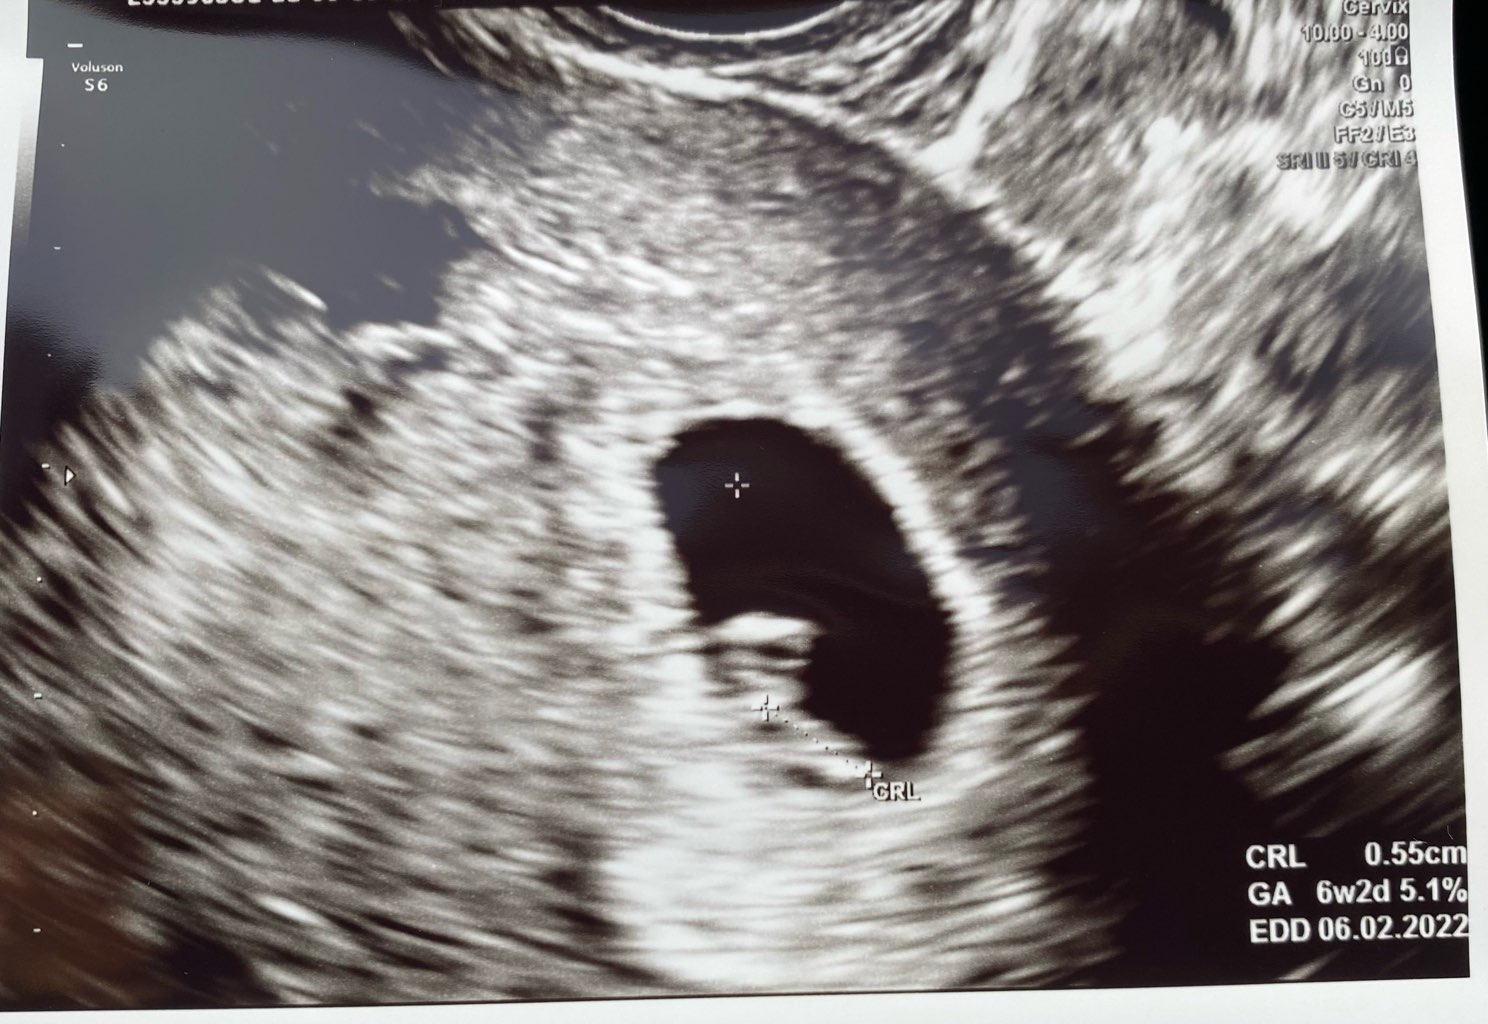

Oki, już po wizycie. Lekarz wstępnie pogratulował ale na razie na USG widoczny tylko pęcherzyk ciążowy. Chyba nawet nie ma tego pęcherzyka żółtkowego

wrzucę wam zdjęcie bo standardowo zapomniałam zapytać. Mój cykl w lutym był trochę dziwny także na razie nie liczymy wieku ciąży z daty OM bo to by wychodził już 6 tydzień pomału a wg wielkości pęcherzyka to tak 4-5

wizyta za 2 tygodnie w poniedziałek. Mam nadzieję że będzie zarodek z pięknym serduchem bo teraz się dygam pustego jaja